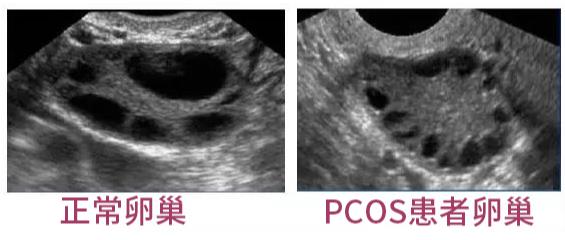

女性不孕的病症中包括输卵管堵塞、卵巢早衰、多囊卵巢等,有一些多囊卵巢患者积极备孕却总是不能怀上宝宝,一想到现在做试管婴儿能辅助生育便想试试。那么,有多囊卵巢可以做试管婴儿吗?

多囊卵巢或多囊卵巢综合征引起的女性不孕的主要原因是排卵障碍。而排卵障碍的治疗,要通过调整生活方式,包括少糖少油、运动、减体重和口服药物治疗来改善代谢和内分泌状态;然后,再通过促排卵治疗来实现卵巢正常排卵。大部分多囊女性在通过上述治疗后,可以顺利受孕。如果还是不行则可以考虑试管婴儿辅助生育。